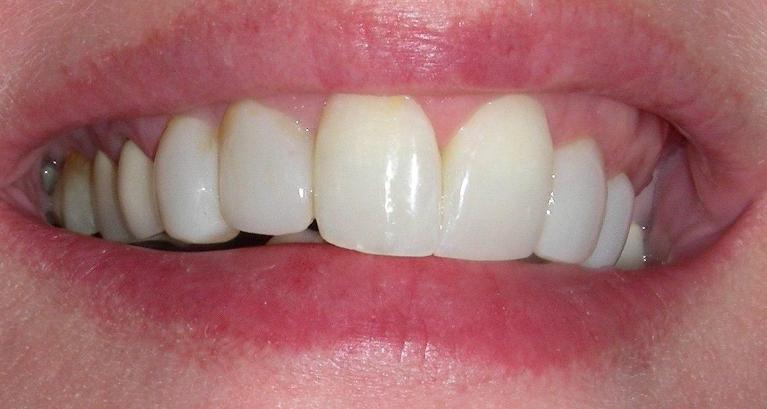

After

Repair of fractured incisor with composite resin.

Composite resin was bonded to the fractured area, and her treatment was completed within an hour.